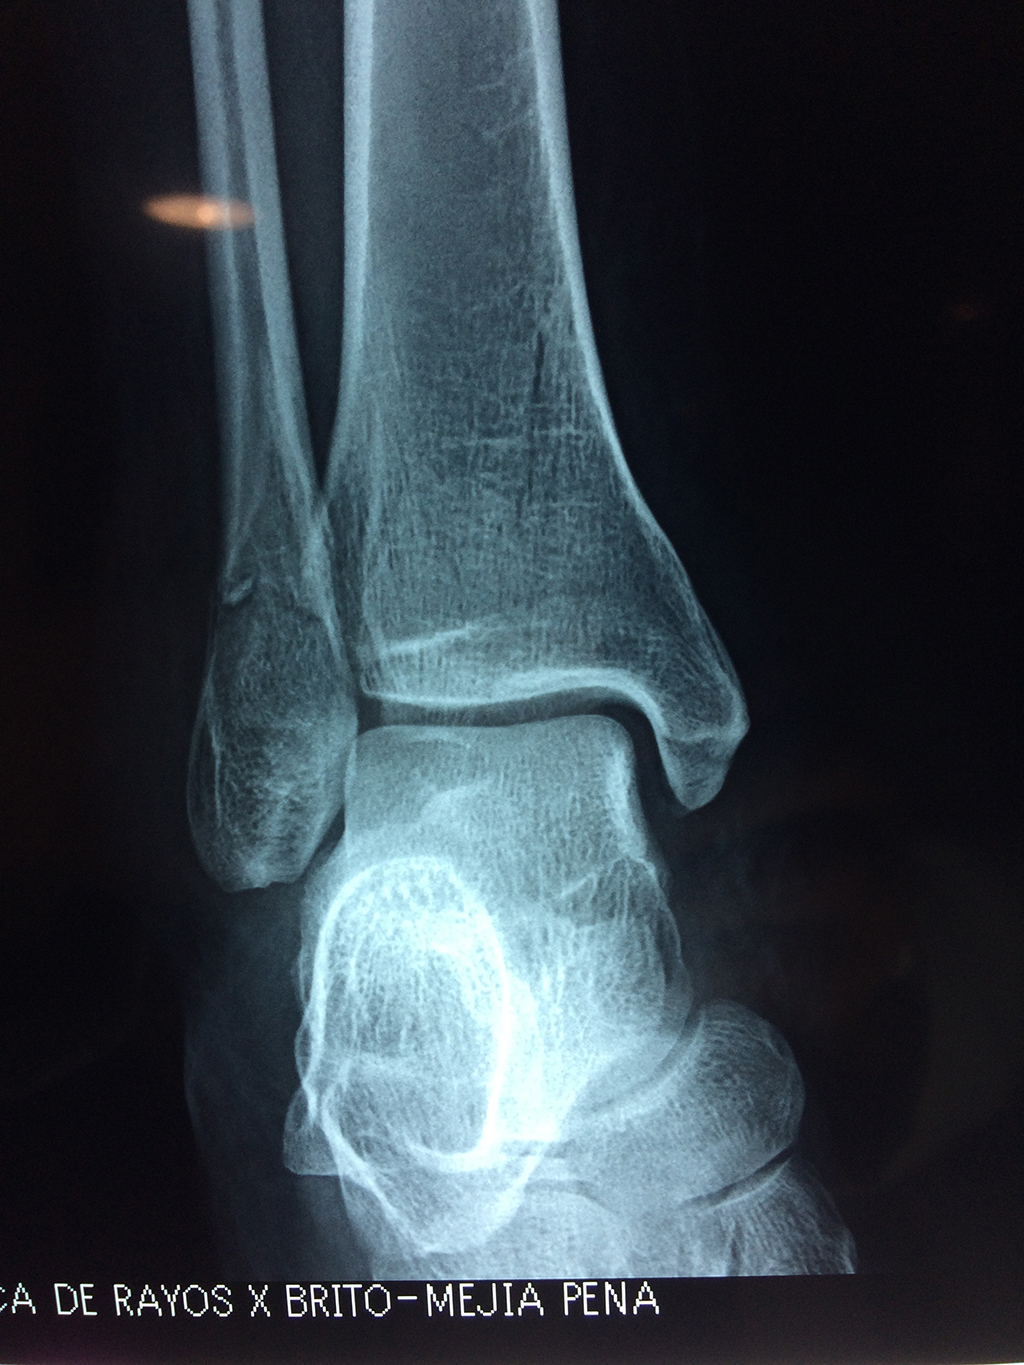

Una fractura de tobillo es la rotura de uno o más de los huesos del tobillo. Estas fracturas pueden ser:

- Parciales (el hueso está sólo parcialmente fisurado, no del todo).

- Completas (el hueso está perforado y está en 2 partes).

- Producirse en uno o ambos lados del tobillo.

Algunas fracturas de tobillo pueden requerir cirugía si:

- Los extremos de los huesos están desalineados entre sí (desplazados).

- La fractura se extiende hasta la articulación del tobillo (fractura intra-articular).

- Los tendones o ligamentos (tejidos que sujetan los músculos y los huesos entre sí) están rotos.